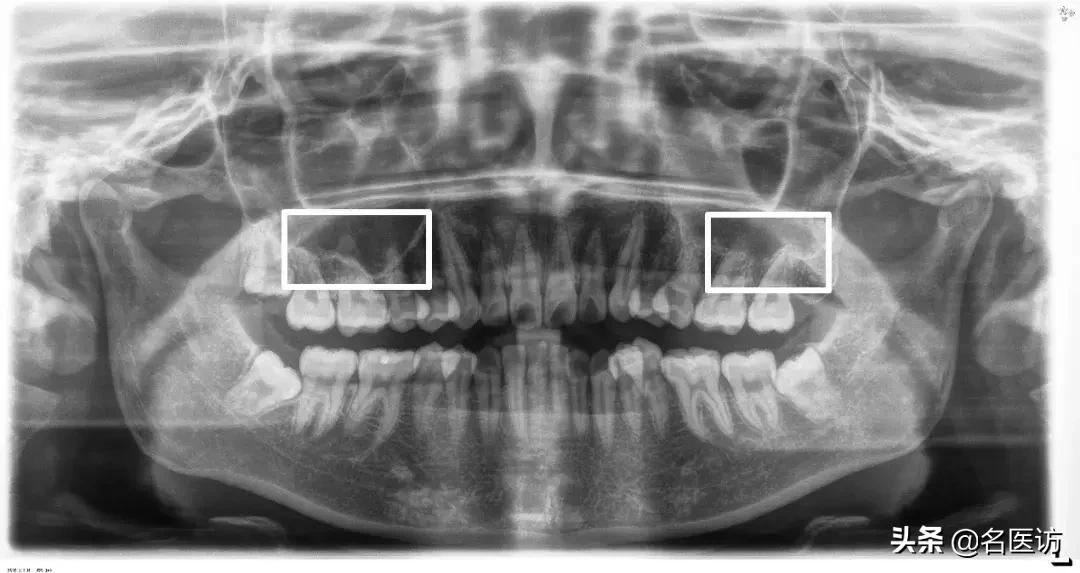

4、上颌窦

上颌窦底与上颌后牙牙根的位置关系也是矫正时要重点关注的,一般来说上颌第一磨牙与上颌窦底距离最近,但两者依然保持着“睦邻友好”的关系,如果上颌牙的某些牙根进入了上颌窦内,那么这些牙齿在矫正时移动的阻力可能会比其他牙齿大很多,可能存在这些牙齿的矫正效果不如预期的情况。另外,即使这些牙齿可以移动,但也会增加牙根吸收、牙齿移动不了的风险。

牙根穿过上颌窦